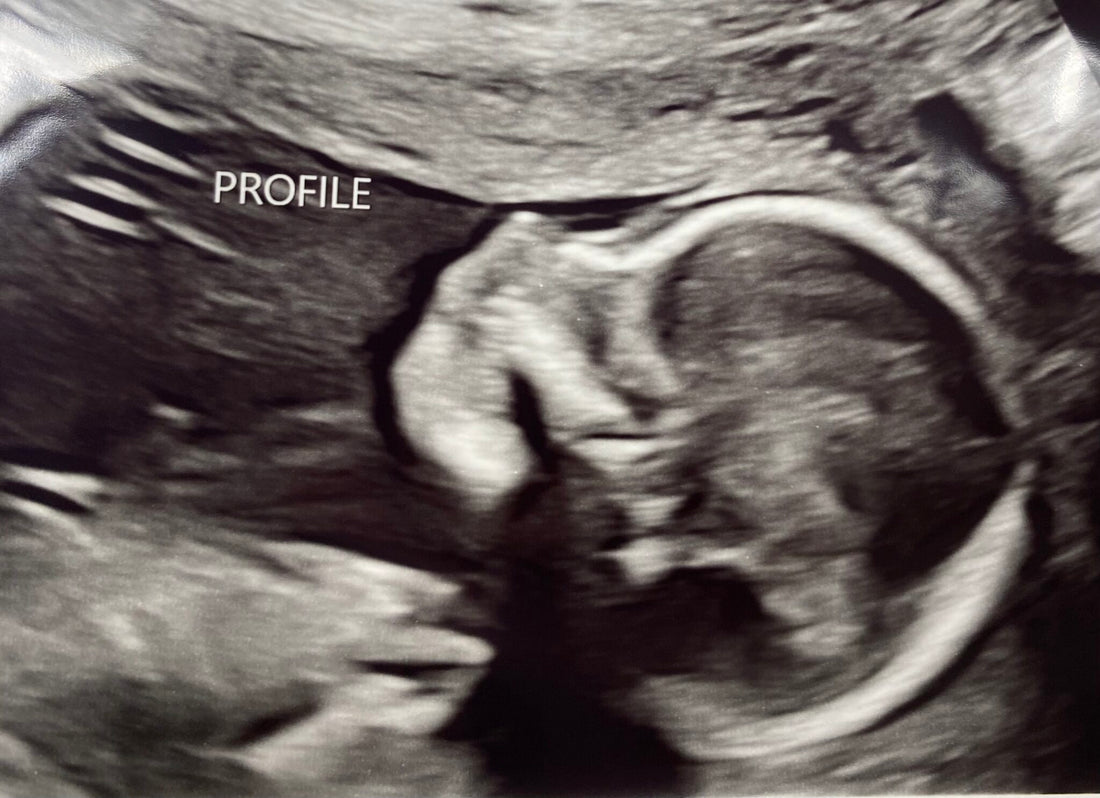

She began telling us it looked like our son, Noah, had spina bifida and some fluid on his brain, also known as hydrocephalus. She said all this with tears in her eyes. I was inconsolable. My husband didn’t know how to react. Being the incredible human and doctor she is, she told us to stay put until she could get in touch with our local maternal-fetal medicine doctor. I’m not sure what kinds of strings she had to pull, but we were in his office about an hour later.

You see, we thought we were just going to the office for our 20-week anatomy scan. We had already done the genetic testing, so we assumed we would just be counting fingers and toes. Man…our assumptions were wrong. You don’t ever expect your baby to have a birth defect until you hear those unfortunate words pass across your doctor’s lips. We received a spina bifida diagnosis that day.

The MFM did another in-depth ultrasound. I feel like it took days to get this scan done. After we had finished, we went into a little room where he graciously walked us through Noah’s condition in specifics. We talked through many options, but he is not a Spina Bifida expert, so we were going to be referred to specialists 4 hours away.